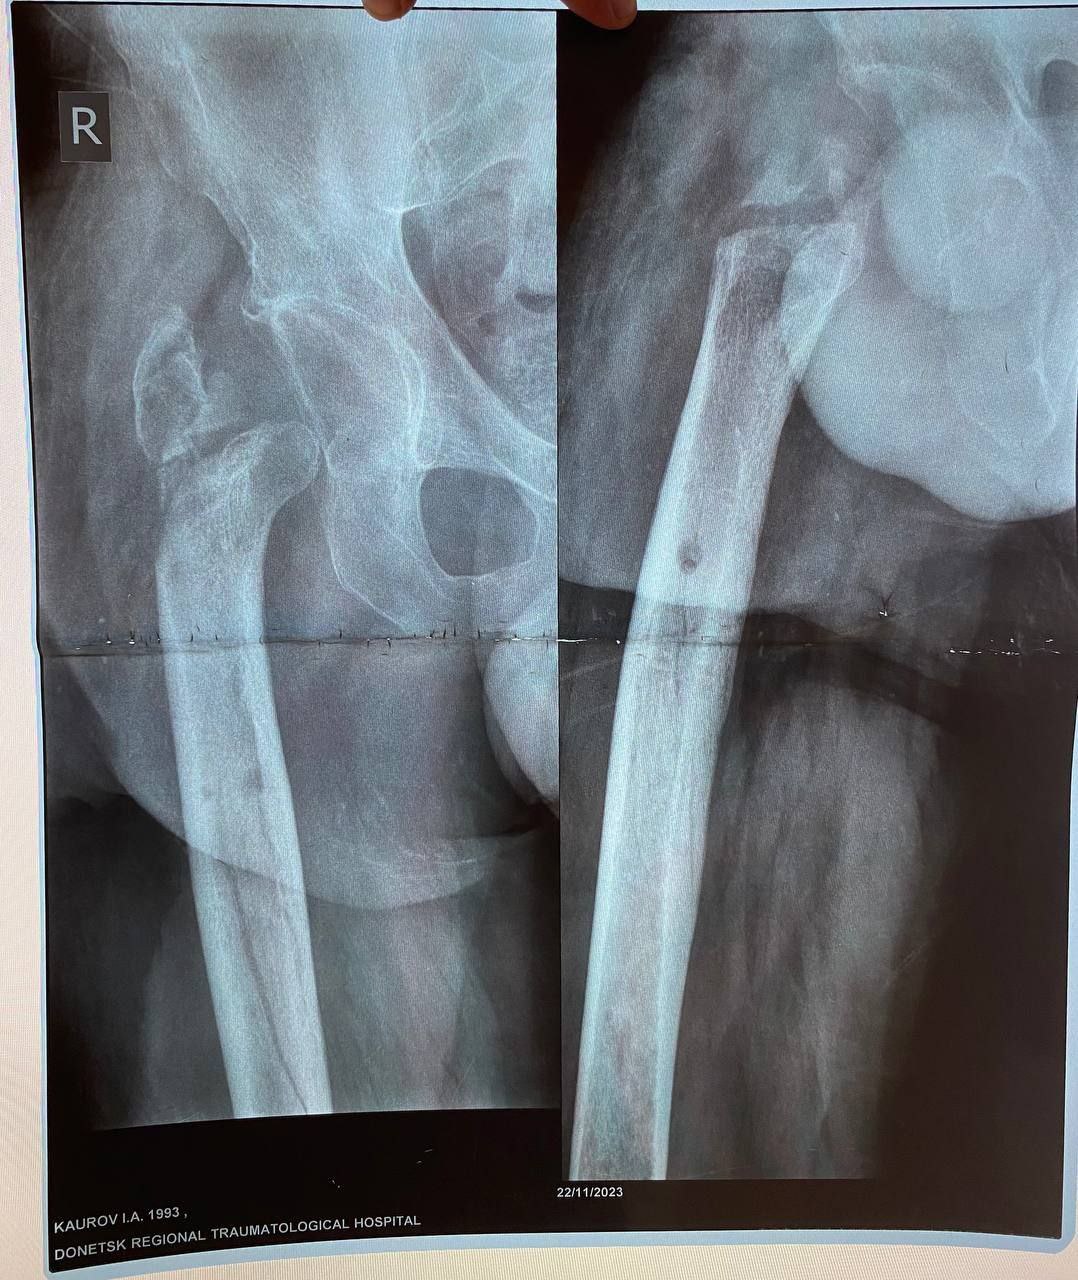

Вместо стандартной замены сустава пациенту выполнили сложнейшее вмешательство с использованием ревизионных систем эндопротезирования, в ЛНР такую операцию провели впервые. Главная задача хирургов заключалась не просто в установке импланта, а в восстановлении биологической оси конечности и компенсации укорочения.

Хирургам пришлось работать в рубцово-измененных тканях после десятка предыдущих операций, убрать очаги инфекции (некроэктомия) и с помощью специальных ревизионных компонентов буквально «собрать» сустав заново, вернув ноге физиологическую длину. Для пациента это означает шанс не просто избавиться от боли, но и забыть о хромоте, вернуться к нормальной походке.

05.03.2026 — Эндопротезирование тазобедренного сустава ревизионными системами с восстановлением оси и длины конечности.